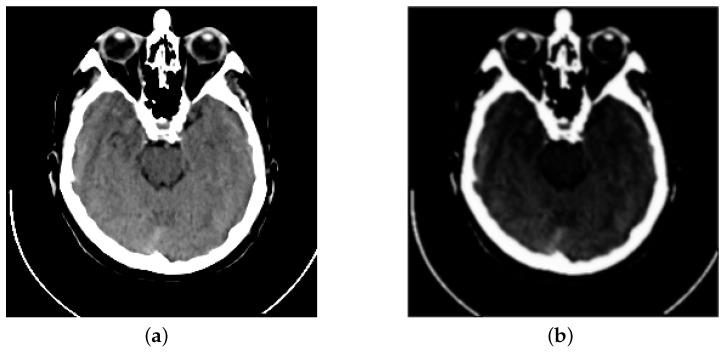

Recently, the rapid development of the Internet of Things has contributed to the generation of telemedicine. However, online diagnoses by doctors require the analyses of multiple multi-modal medical images, which are inconvenient and inefficient. Multi-modal medical image fusion is proposed to solve this problem. Due to its outstanding feature extraction and representation capabilities, convolutional neural networks (CNNs) have been widely used in medical image fusion. However, most existing CNN-based medical image fusion methods calculate their weight maps by a simple weighted average strategy, which weakens the quality of fused images due to the effect of inessential information. In this paper, we propose a CNN-based CT and MRI image fusion method (MMAN), which adopts a visual saliency-based strategy to preserve more useful information. Firstly, a multi-scale mixed attention block is designed to extract features. This block can gather more helpful information and refine the extracted features both in the channel and spatial levels. Then, a visual saliency-based fusion strategy is used to fuse the feature maps. Finally, the fused image can be obtained via reconstruction blocks. The experimental results of our method preserve more textual details, clearer edge information and higher contrast when compared to other state-of-the-art methods.